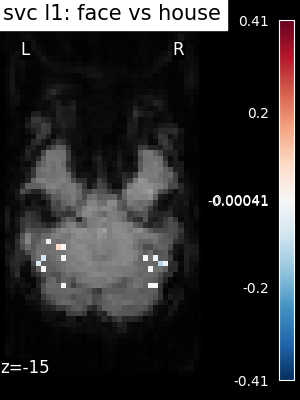

svc(same assvc_l2) : The support vector classifier.svc_l1: SVC using L1 penalization that yields a sparse solution : only a subset of feature weights is different from zero and contribute to prediction.logistic(orlogistic_l2) : The logistic regression with l2 penalty.logistic_l1: The logistic regression with l1 penalty (sparse model).ridge_classifier: A Ridge Regression variant.dummy classifier: A dummy classifier is a classifier that makes predictions using simple rules. It is useful as a simple baseline to compare with other classifiers.

The corresponding weight maps (below) differ widely from one estimator to the other, although the prediction scores are fairly similar. In other terms, a well-performing estimator in terms of prediction error gives us little guarantee on the brain maps.